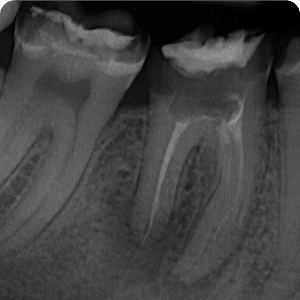

Periapical conditions can also arise when the root canals are not properly filled. In such cases, a root canal re-treatment is performed, which involves refilling the canals. Once correctly filled, these teeth quickly become asymptomatic and remain functional for a long time.